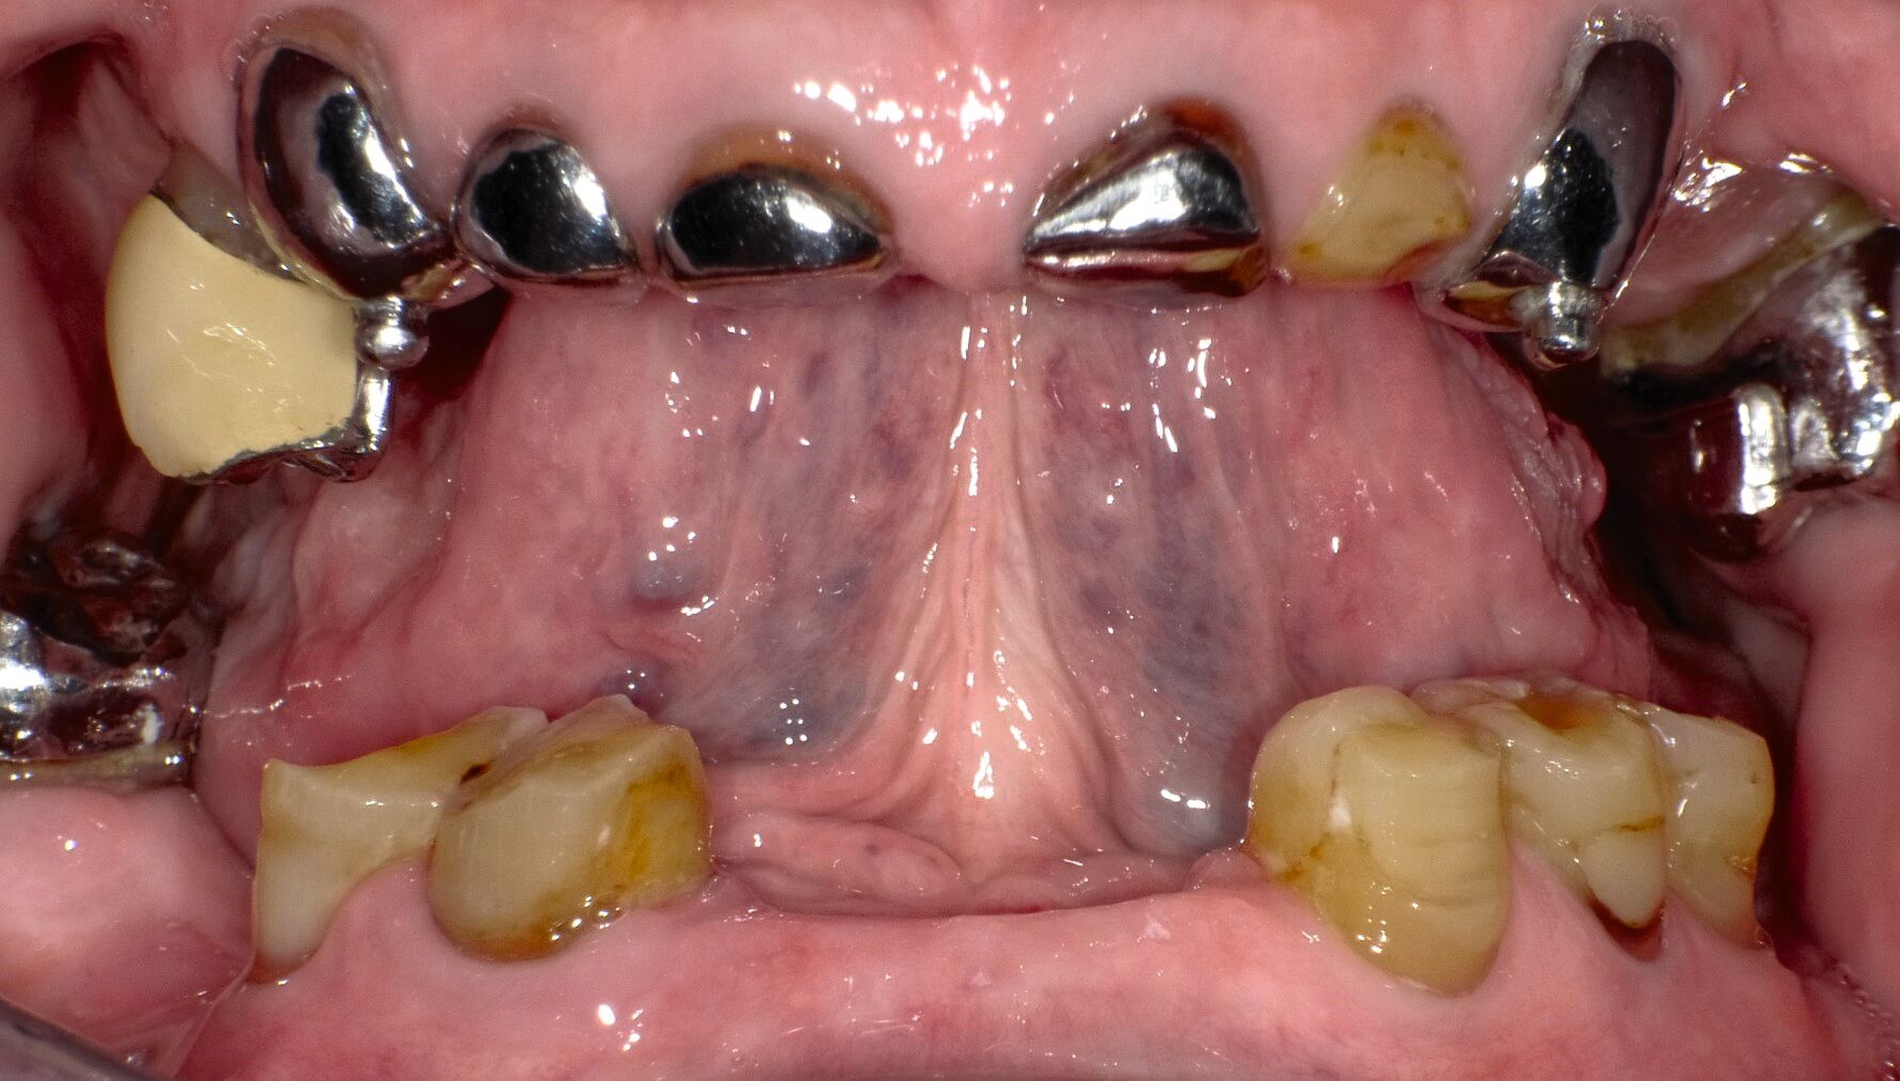

Nach siebenjähriger Tragezeit reduzierte sich der Allgemeinzustand der Patienten bedingt durch einen zweifachen Apoplex erheblich. Die Angehörigen bemühten sich bei nun fehlender Eigenverantwortlichkeit der Patientin um eine dauerhafte Aufnahme in eine Pflegeeinrichtung. Eine Vorstellung zur zahnärztlichen Kontrolle erfolgte nicht und die Patientin konnte unter ihrer ursprünglichen Adresse nicht mehr erreicht werden. Nach eineinhalbjähriger Abwesenheit wurde die Patientin mit Unterstützung ihrer Angehörigen wegen reduzierter Nahrungsaufnahme aufgrund von Schmerzen zur zahnärztlichen Behandlung vorstellig (Abbildung 3). Bei stark reduzierter Therapie- und Mundhygienefähigkeit wurde zusammen mit den Angehörigen entschieden, mehrere stark kariös und parodontal geschädigte Zähne zu entfernen und den vorhandenen Zahnersatz umzuarbeiten. Es lag nun eine BS 3 bis 4 vor.